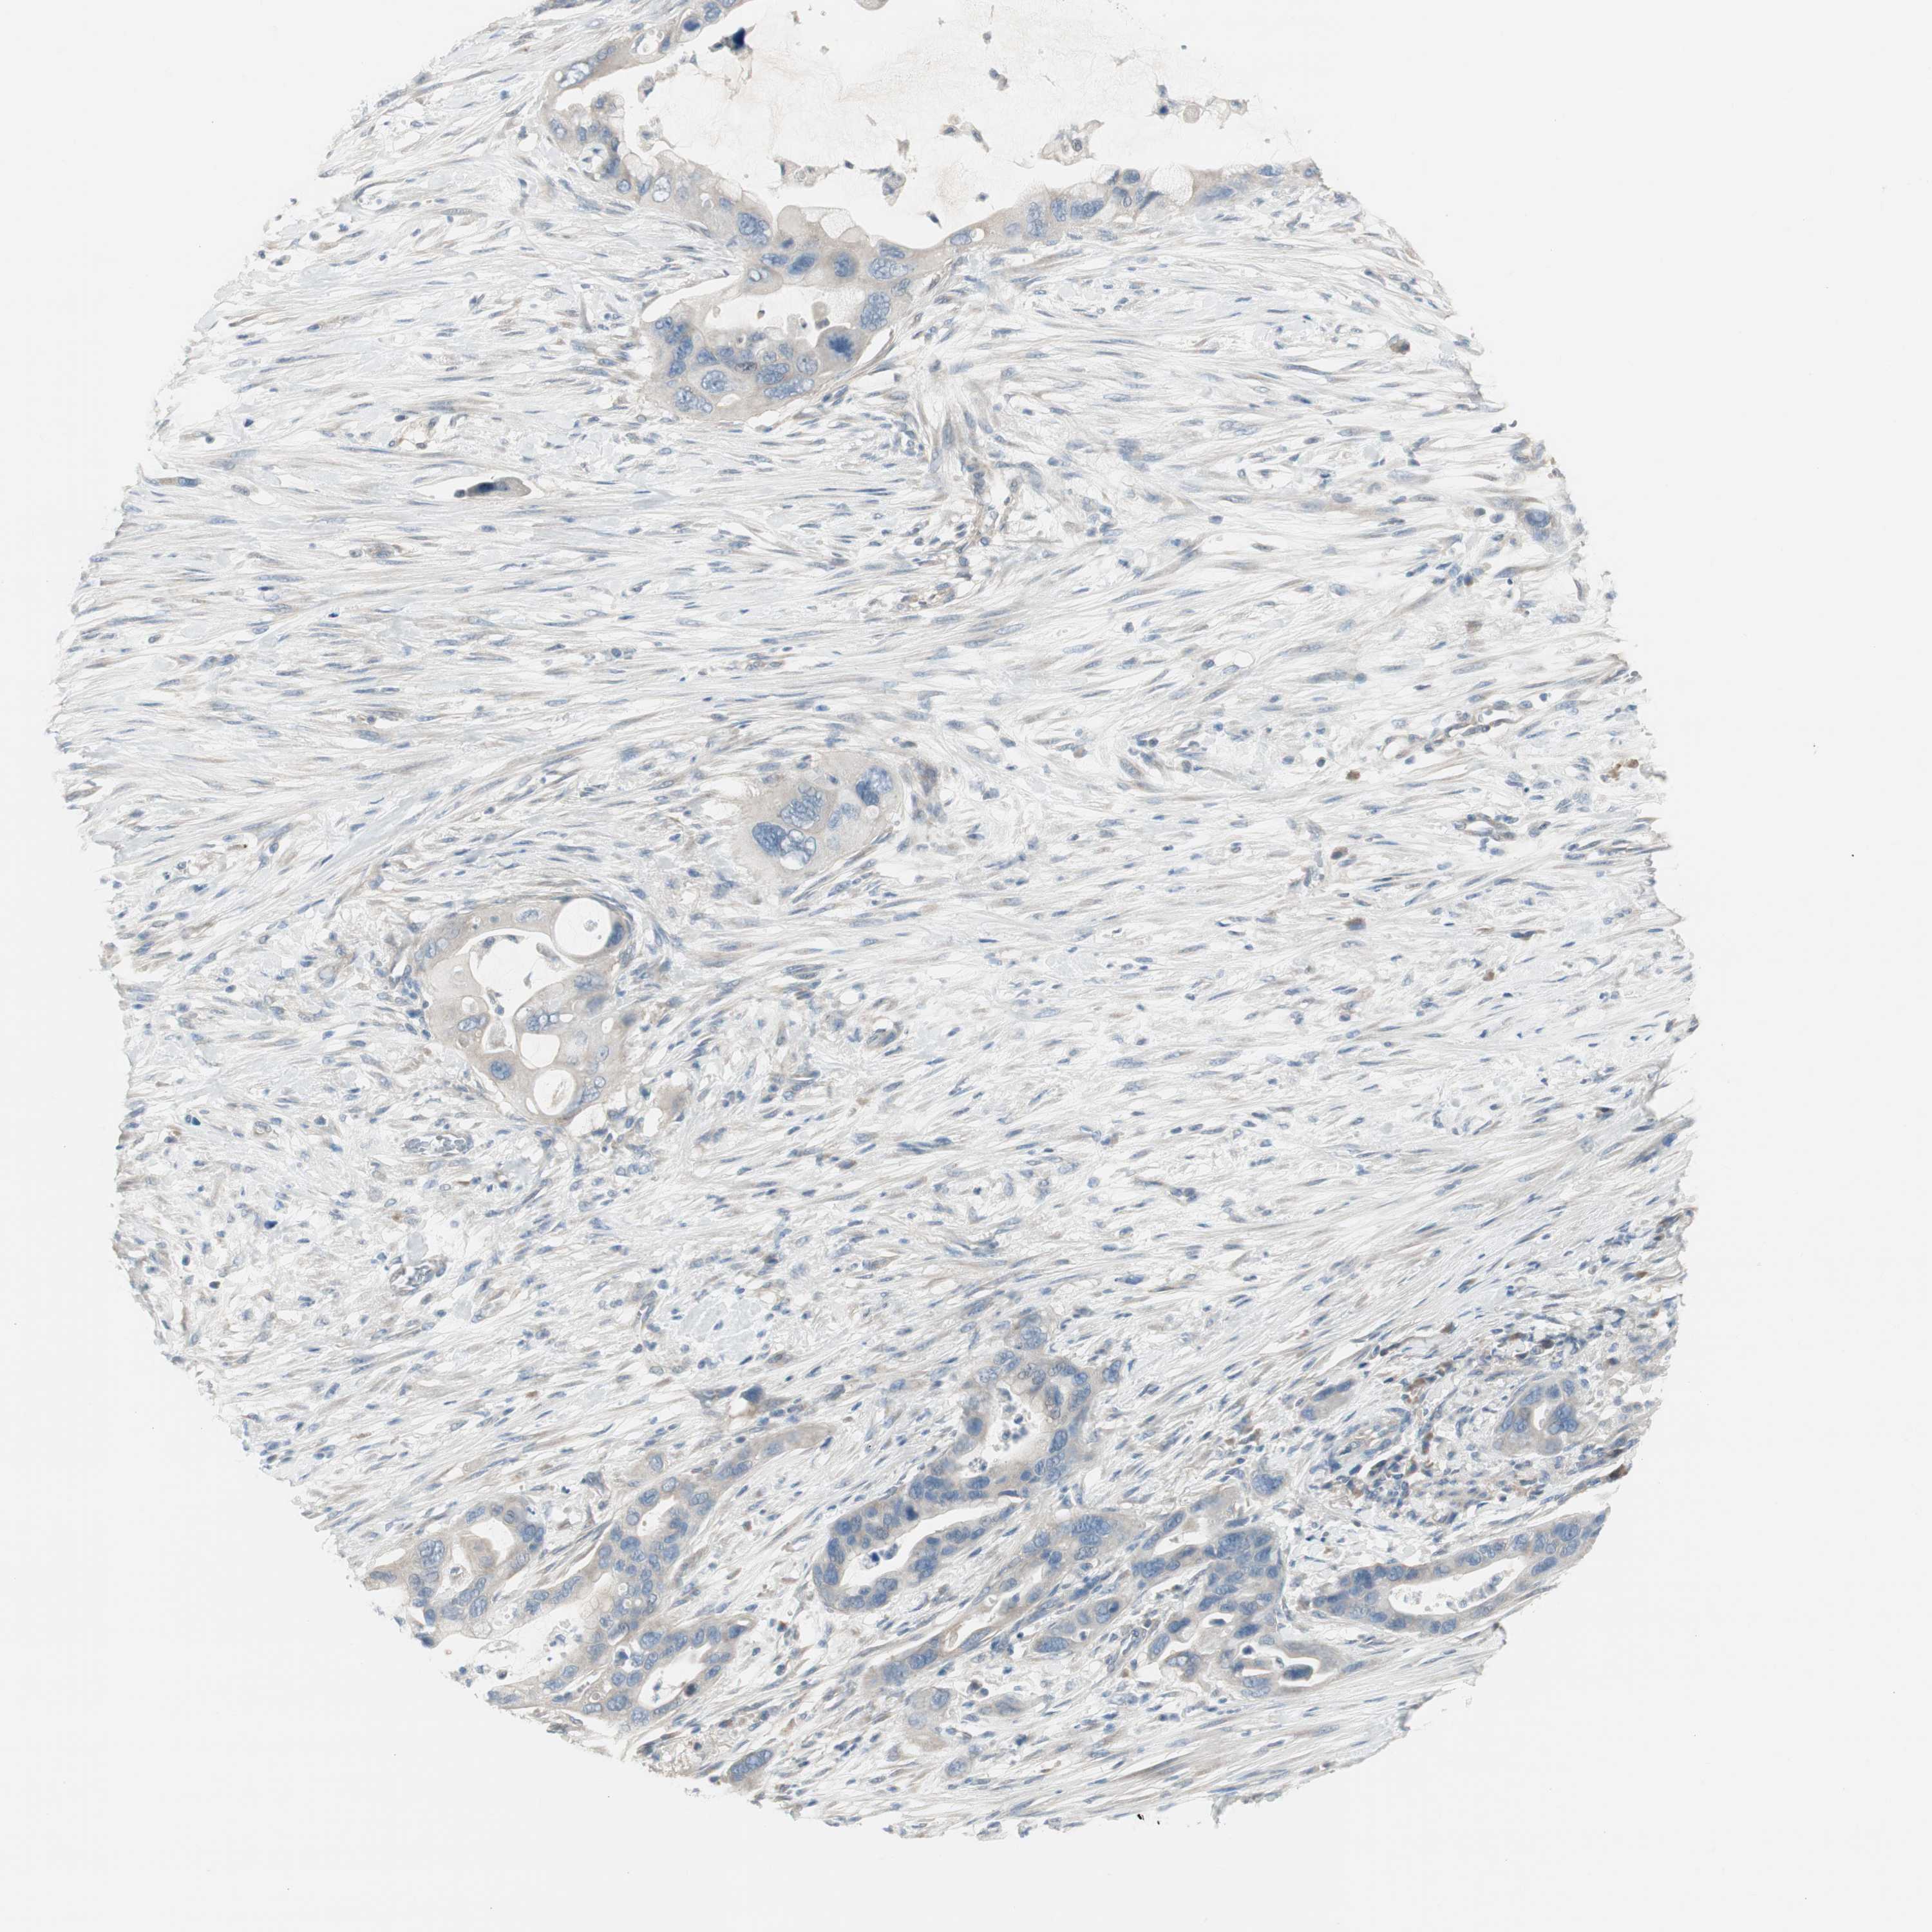

PANCREATIC CANCER - Protein expressioni

A mouse-over function shows sample information and annotation data. Click on an image to view it in a full screen mode. Samples can be filtered based on level of antibody staining by selecting one or several of the following categories: high, medium, low and not detected. The assay and annotation is described here.

Note that samples used for immunohistochemistry by the Human Protein Atlas do not correspond to samples in the TCGA dataset.

Antibody stainingi

Antibody staining in the annotated cell types in the current human tissue is reported as not detected, low, medium, or high, based on conventional immunohistochemistry profiling in selected tissues. This score is based on the combination of the staining intensity and fraction of stained cells.

Each image is clickable and will lead to virtual microscopy that enables deeper exploration of all samples and also displays staining intensity scores, fraction scores and subcellular localization as well as patient and tissue information for each sample.

Antibody HPA008055

Staining

High

Medium

Low

Not detected

Intensity

Strong

Moderate

Weak

Negative

Quantity

>75%

75%-25%

<25%

None

Location

Nuclear

Cytoplasmic/membranous

Cytoplasmic/membranous,nuclear

Adenocarcinoma, NOS

Adenocarcinoma, metastatic, NOS